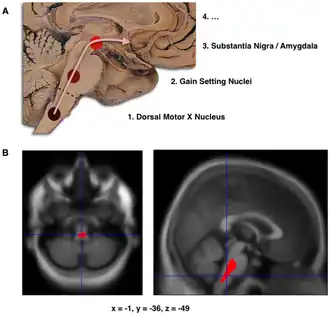

A. Schematic initial progression of Lewy body deposits in the first stages of Parkinson's Disease, as proposed by Braak and colleagues.

B. Localization of the area of significant brain volume reduction in initial PD compared with a group of participants without the disease in a neuroimaging study which concluded that brain stem damage may be the first identifiable stage of PD neuropathology.[1]